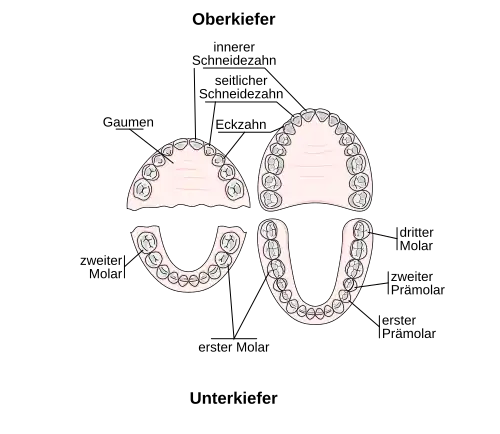

Bei einem Kind besteht das Milchgebiss aus 20 Zähnen, und zwar fünf Zähnen pro Quadrant: dem mittleren und dem seitlichen Schneidezahn, dem Eckzahn sowie dem ersten und zweiten Milchmahlzahn. (Das Gebiss wird in vier Quadranten unterteilt: je ein rechter und ein linker Quadrant, jeweils im Ober- und Unterkiefer.)